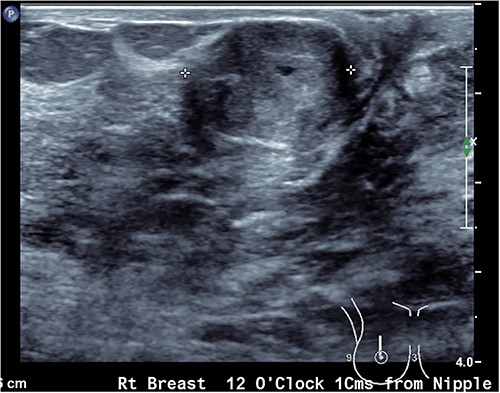

Upon examination, she has B cup breasts. A firm mobile 3 cm lump was palpated at 10 o’clock deep to the areolar edge and there was no palpable axillary lymphadenopathy. The contralateral breast was unremarkable. Ultrasound assessment of the breast demonstrated a lobulated lesion with minimal calcifications measuring 31 × 14 × 19 mm (Figs 1 and 2). No other lesions were detected, and no suspicious lymph nodes were present within the ipsilateral axilla. She proceeded to a core biopsy which demonstrated a fibroepithelial lesion with low cellularity and mitotic figures. A low grade phyllodes tumour could not be excluded based on the core biopsy. Following the discussion of ongoing surveillance, repeat core biopsy or excisional biopsy, the patient decided to proceed with an excision of the lesion.